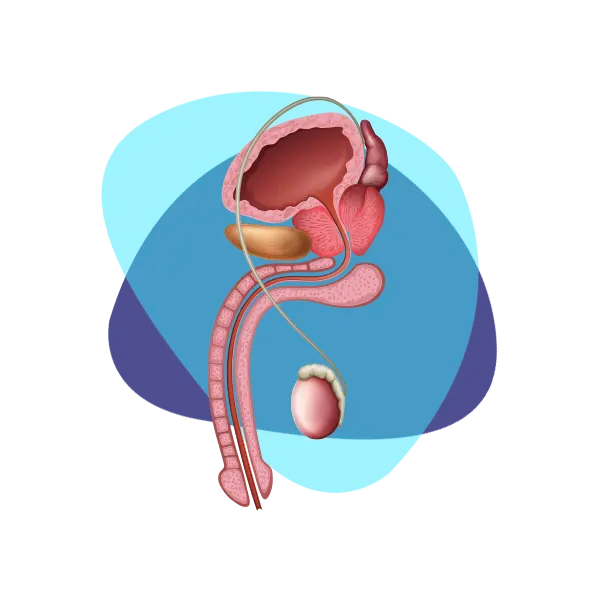

Disfunción eréctil

¿Qué es la disfunción eréctil?

Tener problemas de erección de vez en cuando no significa que una persona padece disfunción, la disfunción se asume cuando una persona tiene este problema de manera recurrente. Es importante mencionar que en muchas ocasiones los problemas de erección son causados por otras enfermedades que requieren tratamiento, como la diabetes, pero también puede ser un factor de riesgo de problemas cardíacos.